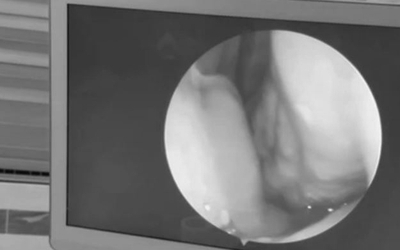

Người đàn ông 60 tuổi liên tục chảy máu mũi, bác sĩ gắp ra thứ "đáng sợ" bên trong

Người bệnh cho biết, ông thường xuyên đi lội suối gần nhà để làm việc. Cách đây vài ngày, ông bắt đầu thấy ngứa, khó chịu và chảy máu mũi kéo dài.